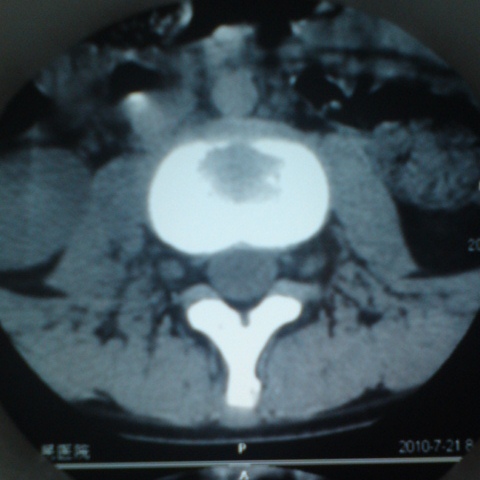

标题: CT27836:女 ,13岁,腰痛数月,加重一月,检查下腰部明显压 [打印本页]

标题: CT27836:女 ,13岁,腰痛数月,加重一月,检查下腰部明显压

结核可能性大

考虑腰椎结核,建议做椎体扫描。

腰椎结核可能性大

考虑腰4椎体结核伴右侧椎旁及椎管右侧硬脊膜外脓肿形成。

骨质破坏+脓肿=结核

结核

考虑腰椎结核伴右侧椎旁及椎管右侧硬脊膜外寒性脓肿形成;建议必要时行mri检查。